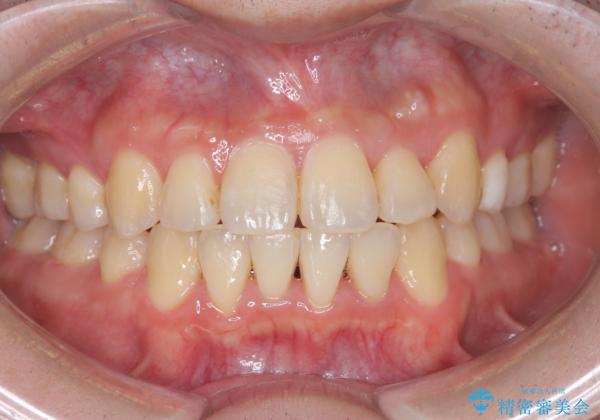

【重度叢生ワイヤー矯正】きれいな歯並びにしたい

- きれいな歯並びにしたいとの希望を持って来院された患者様です。

上下左右小臼歯を抜歯する治療計画を立て審美装置にて治療を行いました。

骨格的3級傾向もあり、咬合関係を仕上げるのに時間がかかりましたが、患者様には大変満足していただけました。

難しいケースでしたが、矯正用アンカースクリューを用いながら、臼歯関係もきれいに仕上げることができました。